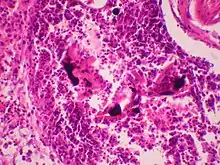

Pode ser feito por sangue e urina para intoxicações recentes ou no cabelo para intoxicações ao longo dos meses. Um nível normal de mercúrio é inferior a 10 ug/L (microgramas/litro) e menos do que 20 ug/L em urina. A concentração de mercúrio no plasma e hemácias podem diferenciar o tipo de mercúrio, pois o mercúrio orgânico nas hemácias é cerca de 20 vezes do que no plasma e a concentração de mercúrio inorgânico é apenas cerca de duas vezes mais, no máximo, do que a encontrada no plasma.[13]